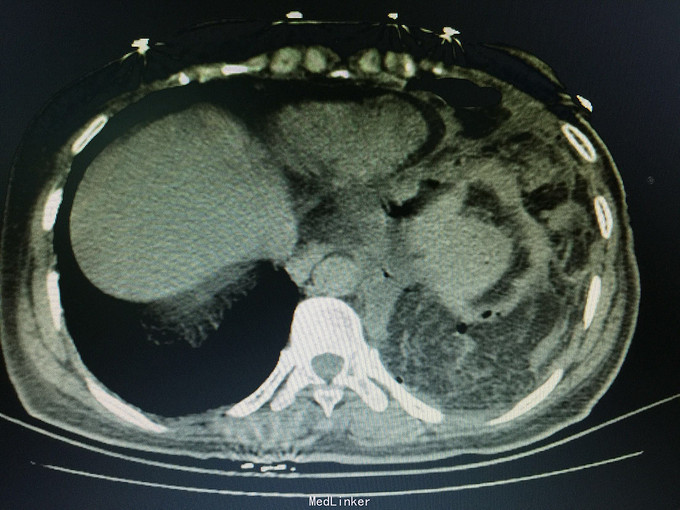

女,41岁, 主诉:腹部胀痛伴不排便、不排气1周, 现病史:一周前无诱因开始腹部胀痛,逐渐加重,以左上腹明显,不排便,不排气,恶心,呕吐数次胃内容物,在当地医院抗炎治疗不见好转,今排腹部平片诊断为“肠梗阻”,来诊。

一般状态可,腹部平坦,未见肠型及蠕动波,脐周压痛,左上腹明显,无腹肌紧张,未及包块,移动性浊音阳性,肠音2次/分。 辅助检查:全腹CT:腹部肠管明显扩张,积液,左侧膈肌局部缺损,腹腔内肠管及系膜组织疝入胸腔。

诊断:膈肌疝,疝内容嵌顿,肠梗阻 处理:手术治疗。